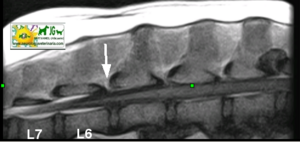

![]() por Juan M. Griñán. Veterinario ![]() comparativa entre una mielografía (mostrando la aguja) y una resonancia magnética, secuencia SE T1w (mostrando donde está el saco dural, sitio para la inyección del contraste). Nótese la extravasación del contraste yodado en la mielografía. | |||||||||